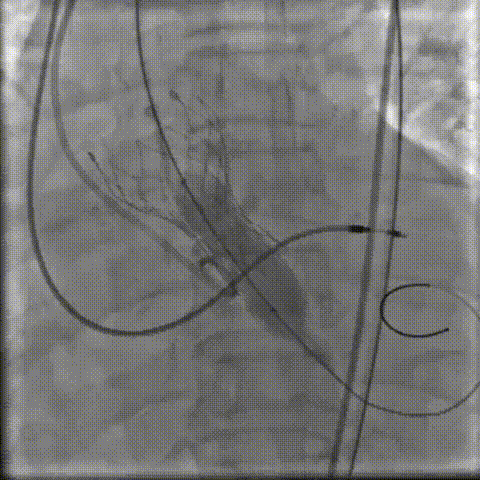

4.定位

9.gif